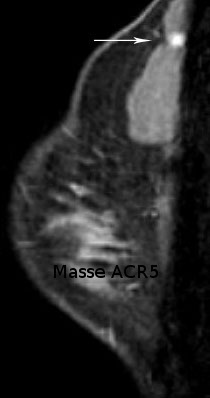

La morphologie de la lésion observée et la visualisation d'une ou plusieurs zones prises de contraste sont les principales informations fournies par l'IRM.

Une image de morphologie irrégulière surtout, et une prise de contraste associée avec courbe de type 5 (prise de contraste précoce, rapide et intense avec phase de lavage secondaire appelée "wash-out") oriente avec une probabilité d'environ 80% vers une lésion maligne (cancer). Selon le contexte médical la morphologie et l’aspect des prises de contraste des lésions peuvent traduire certaines pathologies du sein, notamment de nature cancéreuse.